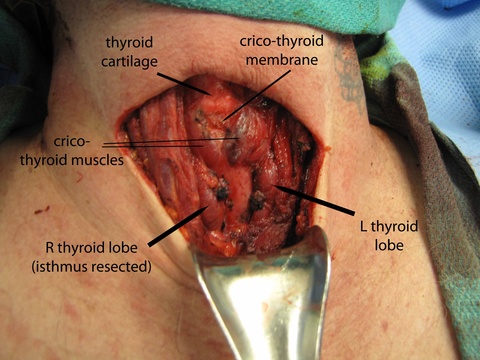

The patient was then prepped (including 1010 drape) and positioned for a central neck dissection thyroglossal duct cyst removal. Just to the left of midline, a large mass was palpated. A 15 blade was used to incise the skin with a horizontal marked incision and down onto the mass. Subplatysmal flaps were raised superiorly and inferiorly down to the area of the thyroid. We divided the straps midline. Of note just to the left of midline, the strap muscles were adherent to the cyst. Inferiorly the cricoid cartilage was identified as well as the thyroid. The mass was dissected around and it appeared to be in continuity with the pyraminal lobe and isthmus. The thyroid was divided to the right and then to the left and tied off with a 3-0 silk running stitch to permit resection of the isthmus in-continuity with the mass extending above.

We dissected the cyst and mass from an inferior to superior direction as it was removed from the cricothyroid muscles and thyroid cartilage up to the hyoid bone with care to avoid the superior laryngeal nerves. A small amount of strap musculateure was removed with the specimen where it was densely adherent on the left side.

Clinical Images